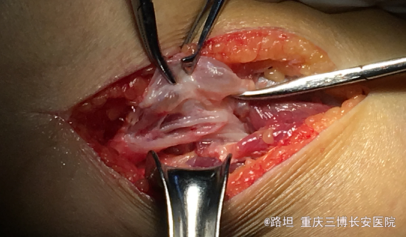

诊断:1.右腓骨头神经鞘膜瘤;2.右侧腓总神经损伤;3.阑尾切除术后; 治疗:硬膜外下行右腓骨头包块切除活检术

神经鞘膜瘤引起腓总神经压迫,足背感觉异常,但是与神经紧密相连,先做活检,再决定是否切除,损伤神经风险高 如何应对术后神经损伤